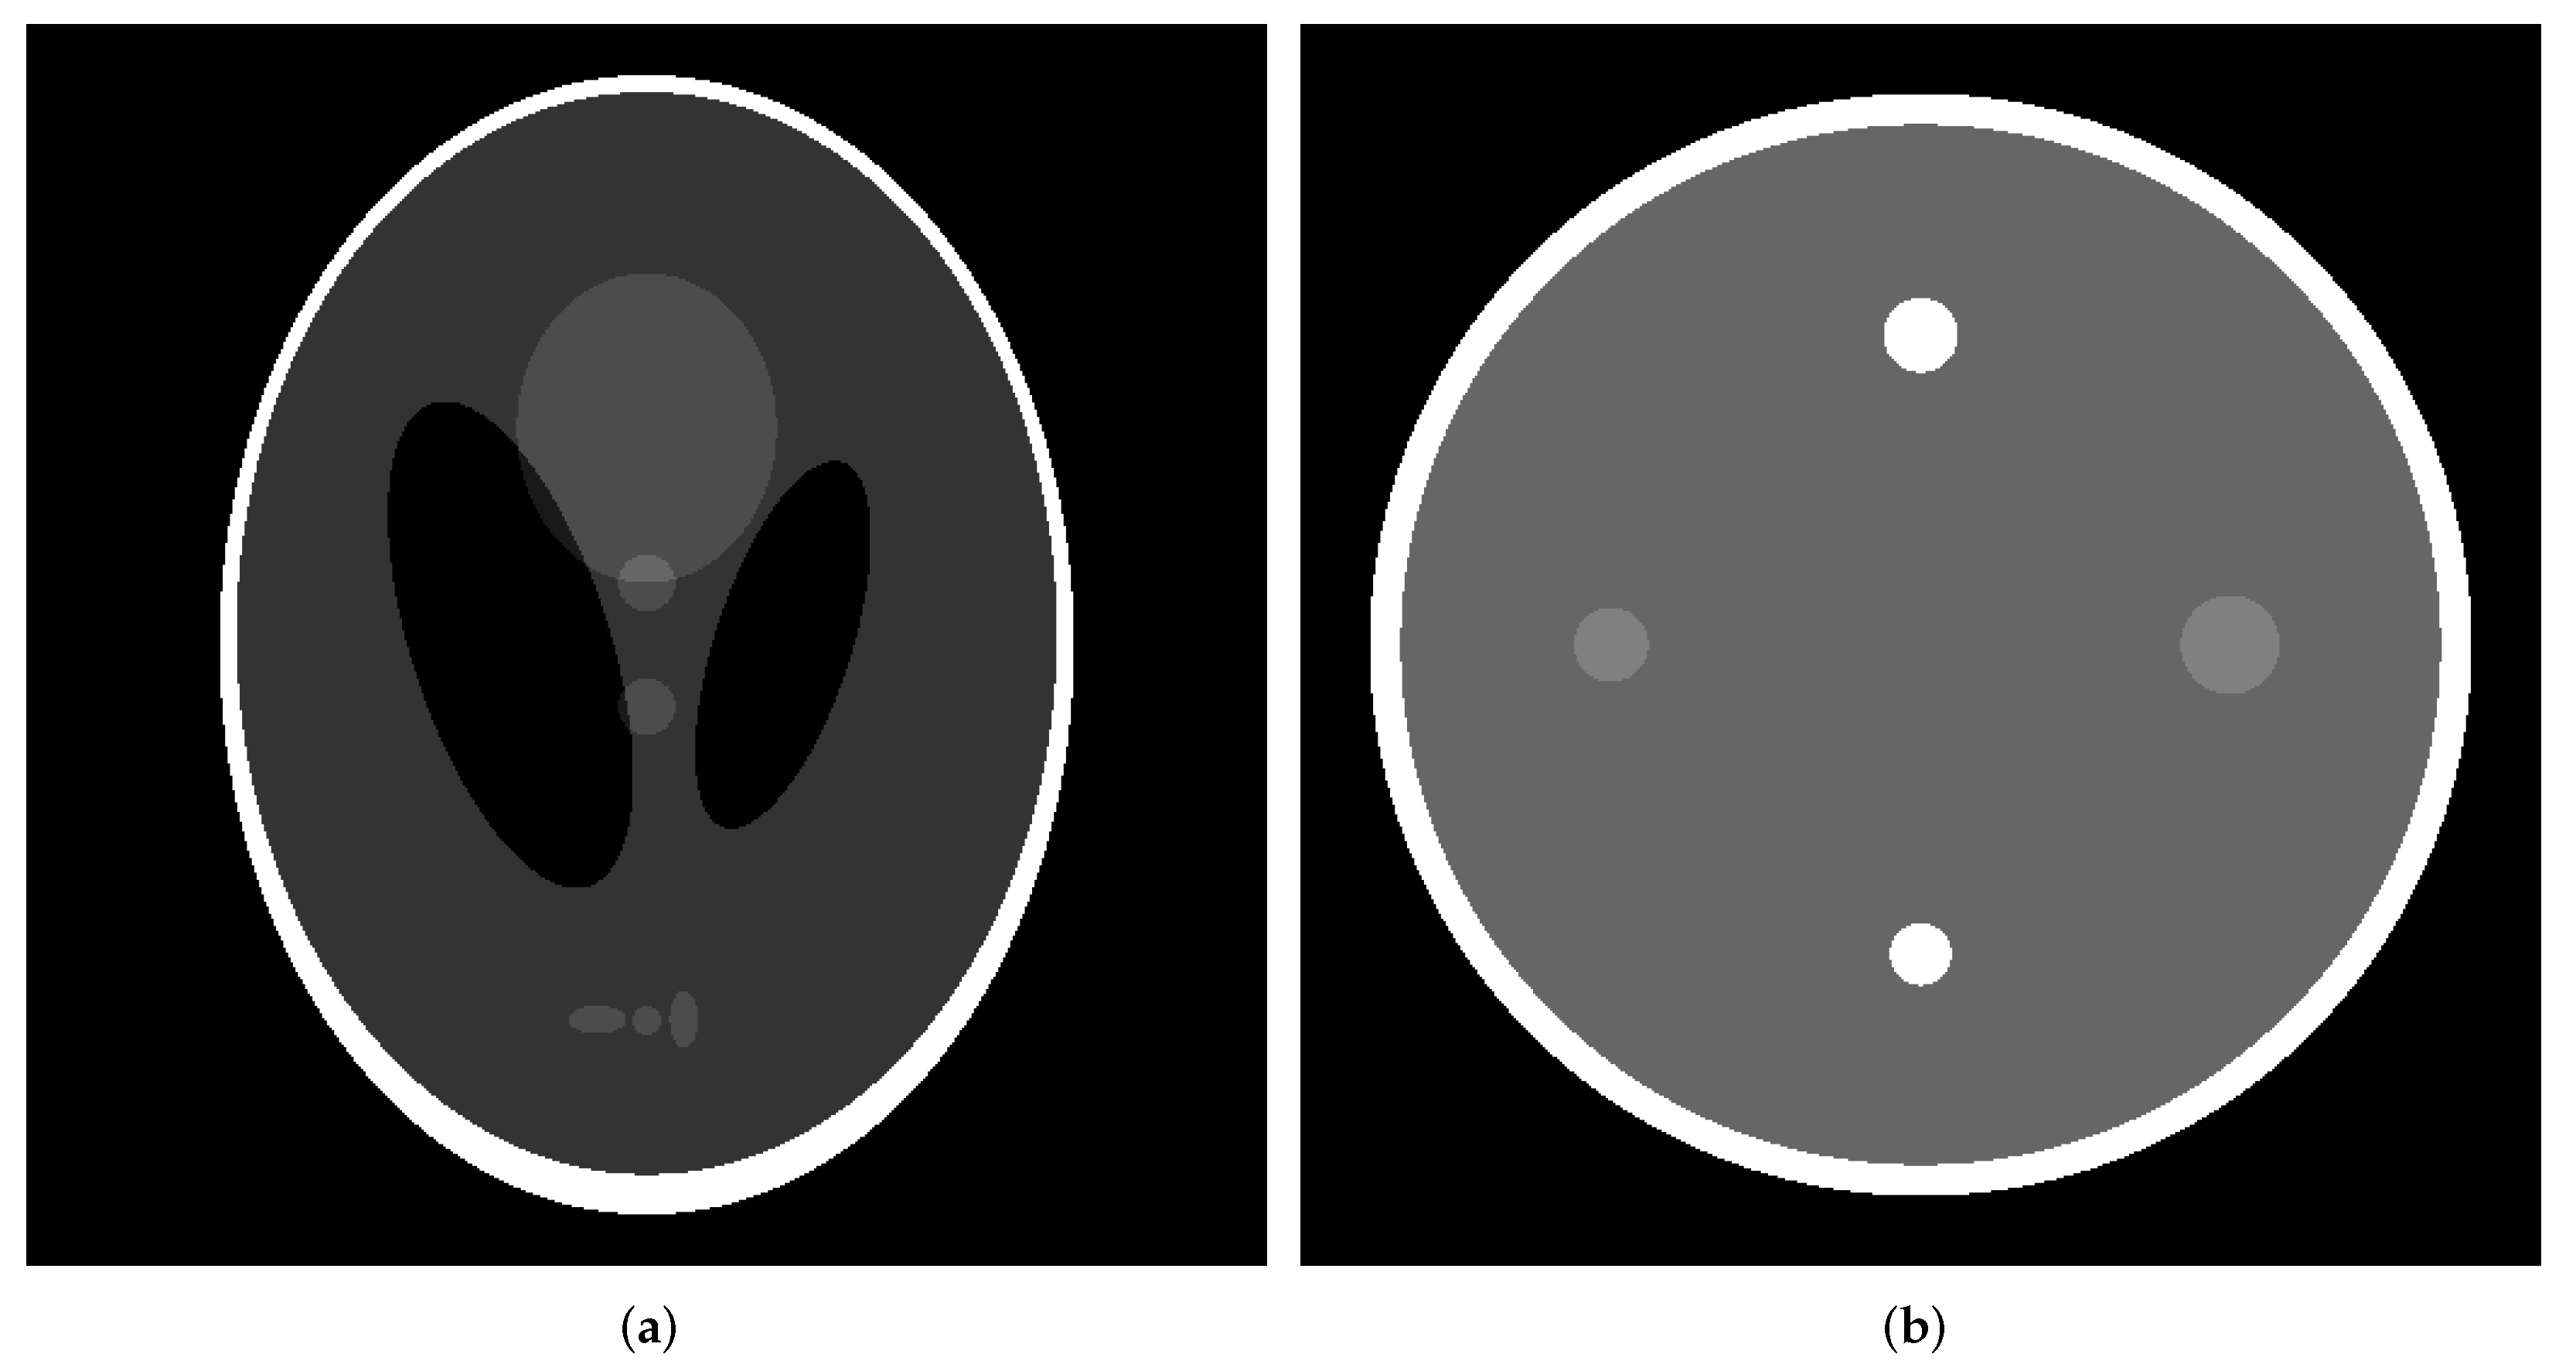

3.1. Numerical Phantom

- Shepp, L.A.; Logan, B.F. The fourier reconstruction of a head section. IEEE Trans. Nucl. Sci. 1974, NS-21, 21–43. [Google Scholar] [CrossRef]